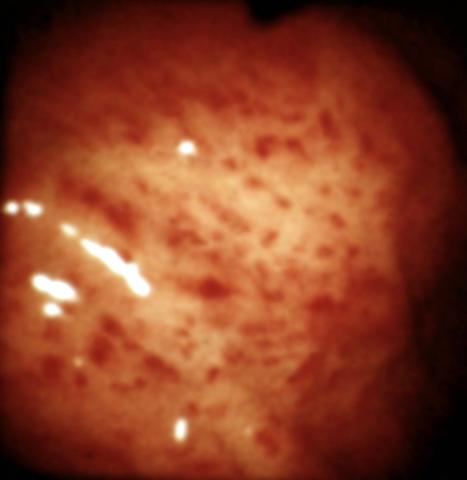

Рис. 3. Эндоскопическая картина желудка в норме и при различных заболеваниях. Поверхностный гастрит: слизистая оболочка желудка отечна, с мелкоточечными очагами гиперемии.